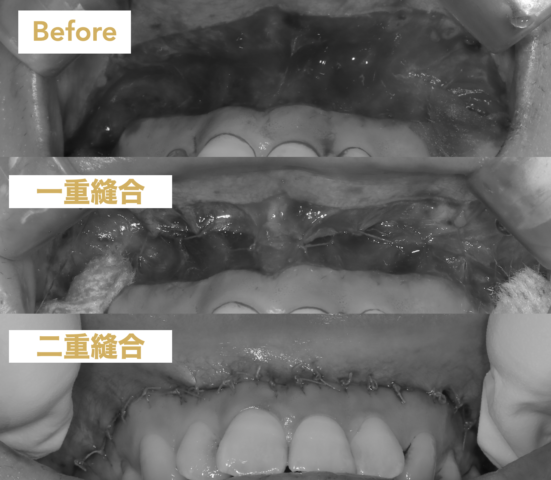

白枠の粘膜を切り取って縫い付けることで笑っても唇を上りにくいようにします。

リップリポジショニングの後戻りを防ぐ骨膜縫合

2024年の9月から内側の骨膜を二重で縫合することで内側からも唇を上らないようにします。この方法により圧倒的に後戻りしにくくなりました!

最新の二重縫合

骨膜縫合と従来の縫合の二重縫合で後戻りを防ぎます。